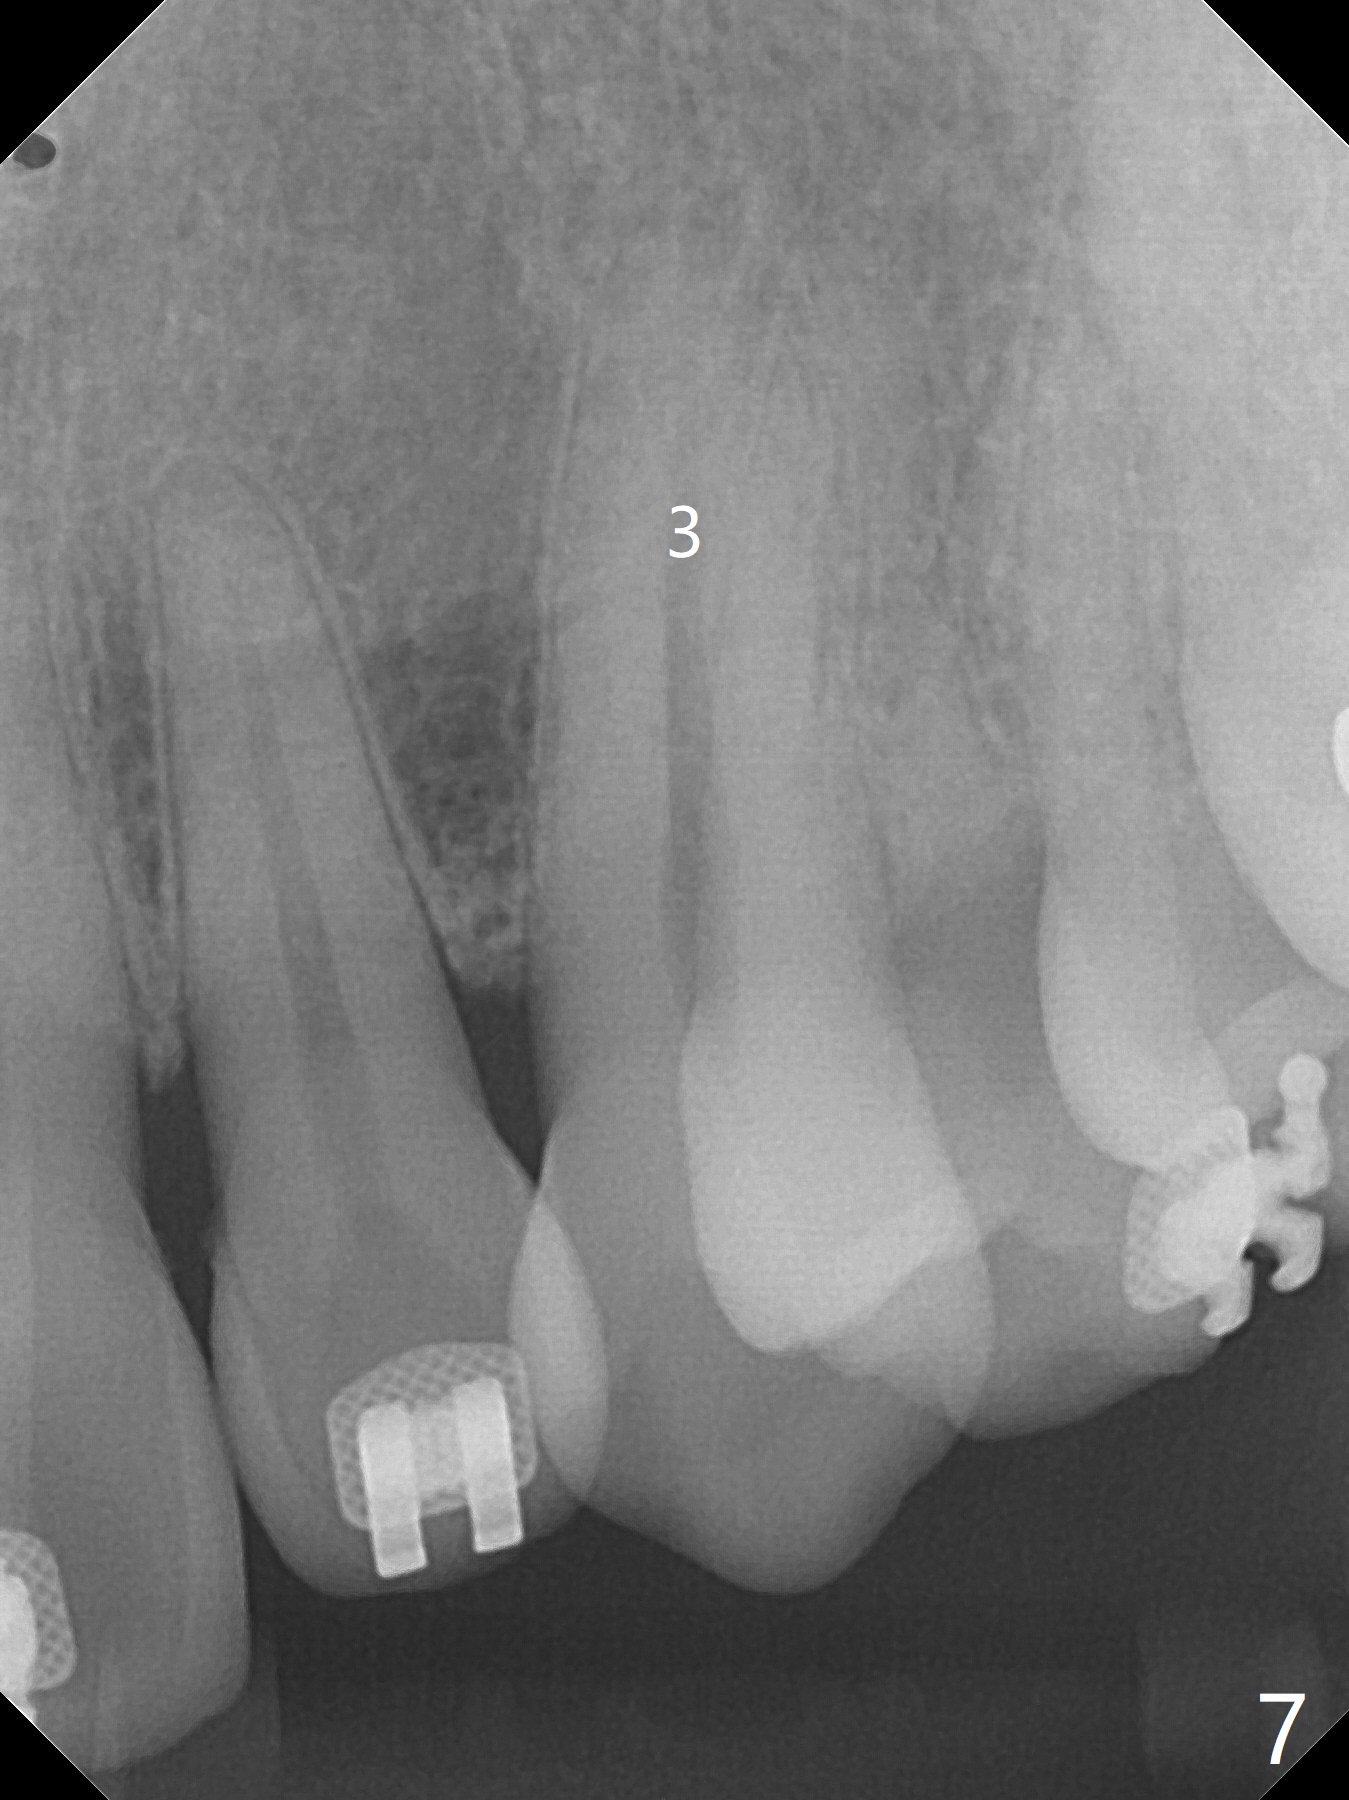

A 40-year-old man requests orthodontics after #17 and 32 extraction. UL5 is missing (Fig.1), while the upper midline deviates to the left (Fig.2 arrow) with crowding between UL2 and 3 (Fig.3). The main goal is to retract UL5 distal and move the upper midline to the right to alleviate UL anterior crowding. Implant will be not needed. To monitor potential root resorption associated with tooth movement, preop PAs are taken (Fig.4-7). The space for an implant at UR5 is narrow. UR4 needs to be distalized using UR7 or a miniimplant distal to UR7 as an anchor (Fig.8). UR4 and 3 will be repositioned to establish Class I occlusion (Fig.9). The space gained by UR4 distalization may be enough to correct the upper midline deviation and UL3 malposition (Fig.10). Brackets will be placed in the lower arch in spite of the normal alignment (Fig.11). UL2 and 3 brackets are unable to be engaged to 14 niti wire (Fig.12). Next visit try to engage UL2 bracket. If not, save the old wire for possible future reuse. Closed spring is placed with 18 ss wire <3 months post banding (coronavirus). Three weeks post closed spring between UR4-7, UR3,4 are being distalized (Fig.13). Distalization of UR4 is not much in 5.5 months (Fig.14,15). It seems necessary to use a miniimplant distal to UR7 as an anchor (Fig.16 white circle), place a long hook mesial to UL4 (more or less root movement instead of tilt) and place the same closed spring between the anchor and hook. In spite of the fact that UR4 seems to have been completely distalized and that UR2 is being distalized 8 months post banding (Fig.18), a 8 mm long mini-implant is placed in the maxillary tuberosity with minimal local anesthetic (Fig.17,19). A longer closed spring (18 mm) is placed between the implant and UR3 hook (Fig.20). Next appointment a lingual button will be placed at UR4 for rotation, while a post hook mesial to UR3 for torque. UR3 distalizes with the help of UR mini-implant, which is unfortunately loose. Next visit place lingual button at UR4 (Fig.21 arrow) to distalize the lingual cusp. Crimpable power hook is placed mesial to UR2 for distalization (for root torque, Fig.22). If it works, remove the wire and reposition the hook for UR1 next visit. UR2 is distalized in one appointment (~ 1 month, Fig.23, as compared to Fig.22). With lingual button at UR4, rotation seems to have been corrected shortly (Fig.24 arrow).